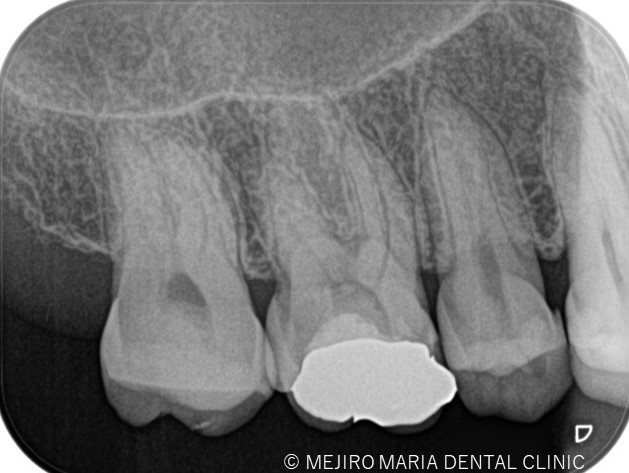

術前の診査より持続性(長い時間)の冷温痛、打診痛を確認し、当院では不可逆性歯髄炎と診断しました。

歯科用拡大鏡、歯科用顕微鏡下にて、軟化象牙質(虫歯)を除去後、歯髄を確認すると一部の歯髄には血流がなく部分壊死を起こしていることがわかる。

|歯の寿命を左右する初回根管治療_術前術後のレントゲン画像比較-1024x756.jpg)